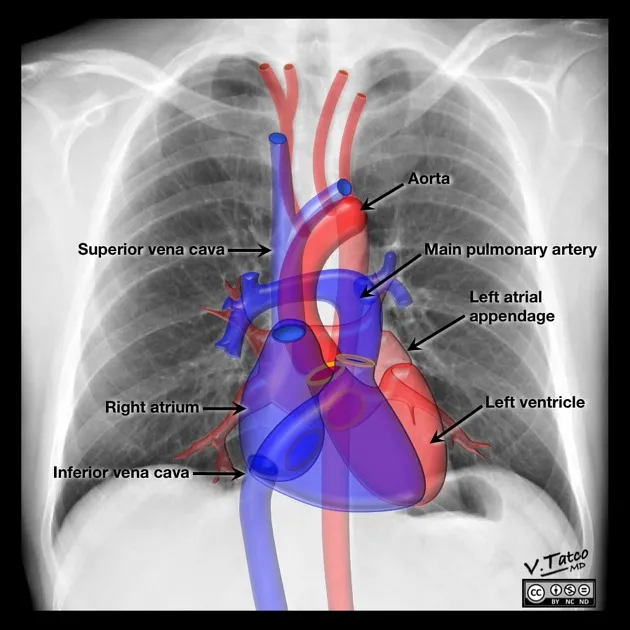

PA View Borders: The heart's edges are formed by specific chambers and great vessels.

- Right: Superior Vena Cava (SVC) and the Right Atrium (RA).

- Left: Aortic knob, main Pulmonary Artery, Left Atrial appendage, and the Left Ventricle (LV).

The cardiac silhouette on a PA chest X-ray presents distinct borders formed by different chambers and great vessels.

- Right Heart Border: Primarily formed by two convexities.

- Superior: Superior Vena Cava (SVC)

- Inferior: Right Atrium (RA)

- Left Heart Border: Composed of four "bumps" or convexities.

- Aortic Knob: The arch of the aorta.

- Main Pulmonary Artery (MPA): The "pulmonary bay".

- Left Atrial Appendage (LAA): Not always visible; enlargement suggests mitral stenosis.

- Left Ventricle (LV): Forms the cardiac apex.

- 📌 Mnemonic (Superior to Inferior): All People Love Lunges